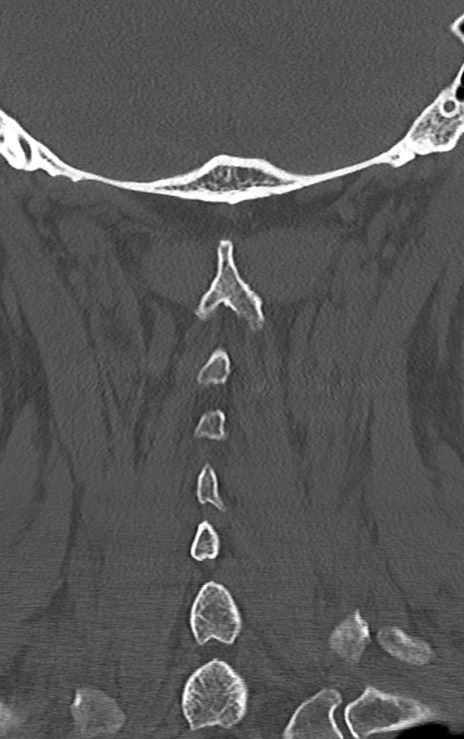

頚椎CT

矢状断像